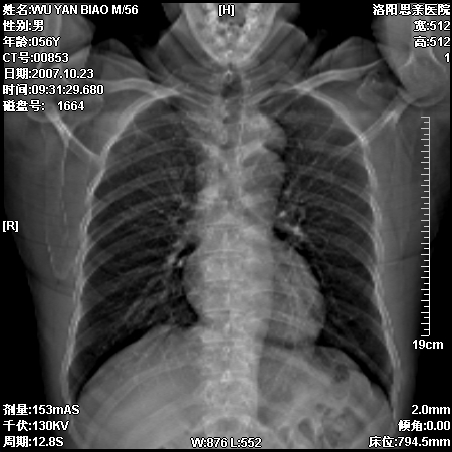

标题: CT10160:M56Y,体检发现,病人无不适,病人随访中 [打印本页]

标题: CT10160:M56Y,体检发现,病人无不适,病人随访中

前上后纵隔神经原性肿瘤,建议增强扫描

后上纵隔占位,与肺交界清,宽基底附着脊柱,密度均匀,局部骨质无明确改变.

考虑;神经源性肿瘤,---起源交感n链?,不除外肠源性囊肿.

与纵隔关系密切,密度均匀。只能考虑:后纵隔神经原性肿瘤!

后纵隔神经原性肿瘤可能性大,孤立性胸膜间皮瘤待排.

1、病灶在后纵隔脊柱旁沟内,此处是神经原性肿瘤的好发部位

2、病灶边缘光滑整齐,更说明病灶来于纵隔,由于有胸膜的包裹所以才导致这么光滑的边缘

3、病灶内的密度均匀